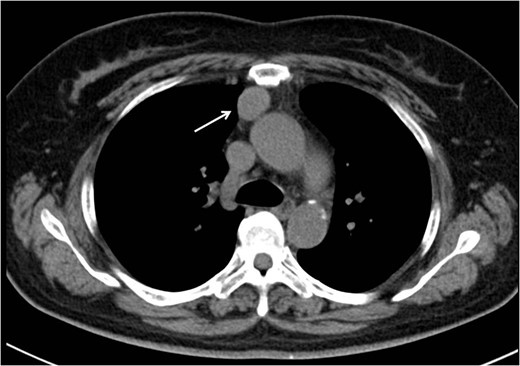

A 60-year-old woman was referred to our hospital with an anterior mediastinal tumor on computed tomography (CT) performed for follow-up 6 years after a complete response to chemotherapy for malignant lymphoma. CT revealed a tumor in the right anterior mediastinum with a diameter of 3.5 cm, round shape and demarcation from the neighboring tissue (Fig. 1). No recurrent lesion of the malignant lymphoma was detected. She had no symptoms, including none due to myasthenia gravis. Her anti-acetylcholine receptor antibody level was 0.2 nmol/L (within normal range). To confirm the diagnosis and treat the patient, we planned tumor resection via VATS.

Initial CT revealed a tumor in the right anterior mediastinum with a diameter of 3.5 cm, round shape, which was clearly demarcated from the neighboring tissue.